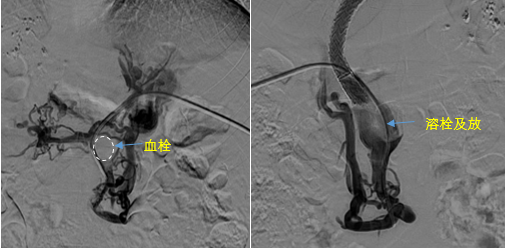

在西安國(guó)際醫(yī)學(xué)中心醫(yī)院,韓國(guó)宏教授對(duì)李女士進(jìn)行了細(xì)致的問診及檢查,在CT圖像上仔細(xì)的分析,針對(duì)患者特殊的病情制定了詳細(xì)的治療方案。第一次進(jìn)入手術(shù)室,在DSA的監(jiān)測(cè)下,造影過程中門靜脈血栓的輪廓逐漸顯現(xiàn)出來,見多識(shí)廣的醫(yī)生們也大吃一驚,發(fā)現(xiàn)遠(yuǎn)端脾靜脈及腸系膜上靜脈也存在大量血栓?;颊叩氖彻芪傅嘴o脈曲張非常嚴(yán)重,疏通堵塞的門靜脈已是刻不容緩。

見此情形,韓國(guó)宏教授憑借豐富的臨床經(jīng)驗(yàn)很快調(diào)整了策略,在超聲診療中心的協(xié)助下進(jìn)行門靜脈右支穿刺,并進(jìn)行造影,看到目標(biāo)血管后,韓國(guó)宏教授用“明修棧道,暗渡陳倉(cāng)”的方法,讓來自脾臟和胃腸的血流終于暢通的回流到了肝靜脈。通過血流的沖刷以及抗凝溶栓藥物的作用,幾日后復(fù)查造影發(fā)現(xiàn)門靜脈血栓已逐漸變小,不會(huì)對(duì)回流到肝臟的血流產(chǎn)生大的阻礙作用,門靜脈的壓力顯著減小,患者再次出血的幾率也隨之降低。幾經(jīng)周折,這顆“定時(shí)炸彈”終于被拆除,李女士和她的家人多年來心里的石頭也終于落地。